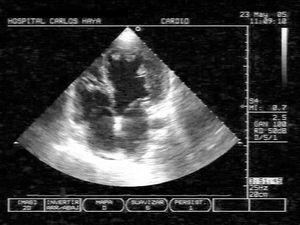

Con la sospecha diagnóstica de MNC al paciente se le realizó una segunda ecocardiografía por personal especializado. La ecocardiografía-2D confirmó la presencia de marcada trabeculación del VI, localizada en ápex y segmentos medios de la pared lateral e inferior, con una relación telesistólica de 2,5 entre la gruesa capa interna de miocardio no compactado (NC) y la fina capa externa de miocardio compactado (NC/C > 2) (fig. 2). Con doppler color se visualizó el flujo de sangre en comunicación entre los profundos recesos intertrabeculares y la cavidad ventricular. El flujo diastólico mitral mostró un patrón restrictivo. El VI tenía morfología esferoidal y medía en telediástole 70 mm, la aurícula izquierda 47 mm y el VD 30 mm. Un flujo de regurgitación mitral fue valorado como insuficiencia mitral moderada, y la presencia de insuficiencia tricuspídea permitió calcular un gradiente AD-VD de 55 mmHg, estimándose una presión de AP de 65 mmHg. No se detectaron anomalías valvulares estructurales. No se consideró necesario realizar una ecocardiografía con contraste dada la buena calidad de las imágenes de la bidimensional1.

Figura 2. Ecocardiograma transtorácico bidimensional en proyección apical de 4-cámaras, que muestra numerosas trabeculaciones prominentes y recesos intertrabeculares (miocardio no compactado) localizados en el ápex y pared lateral de un ventrículo izquierdo remodelado con morfología esferoidal. La relación entre la capa interna de miocardio no compactado y la capa externa de miocardio compactado es mayor de 2 en telesístole.